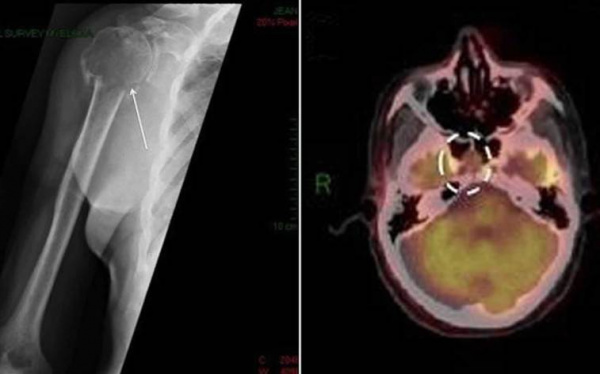

(Слева) При МРТ Т1ВИ в сагиттальной проекции у мужчины 61 года визуализируется крупное солитарное объемное образование, распространяющееся на скат затылочной кости, облитерирующее клиновидную пазуху и прорастающее сзади в полость носа и носоглотку. Плазмоцитома слегка гиперинтенсивна по сравнению с паренхимой головного мозга.

(Справа) При МРТ Т1ВИ с КУ в сагиттальной проекции определяется неоднородное контрастирование новообразования, признаки некроза отсутствуют. Сзади от опухоли отмечается утолщение твердой мозговой оболочки, проросшая в эпидуральное пространство опухоль начинает сдавливать продолговатый мозг. (Слева) При корональной КТ в костном окне у женщины 45 лет с жалобами на боли в области придаточных пазух носа определяется распространенное объемное образование, центр которого локализуется в левой половине клиновидной кости. Новообразование простирается медиально в клиновидную пазуху и вызывает эрозию медиальной стенки средней черепной ямки. Края опухоли относительно четкие, и в некоторых участках в виде яичной скорлупы определяется сохранившийся тонкий кортикальный слой кости.

(Справа) При корональной МРТ Т1ВИ с КУ наблюдается равномерное контрастирование этой плазмоцитомы основания черепа.